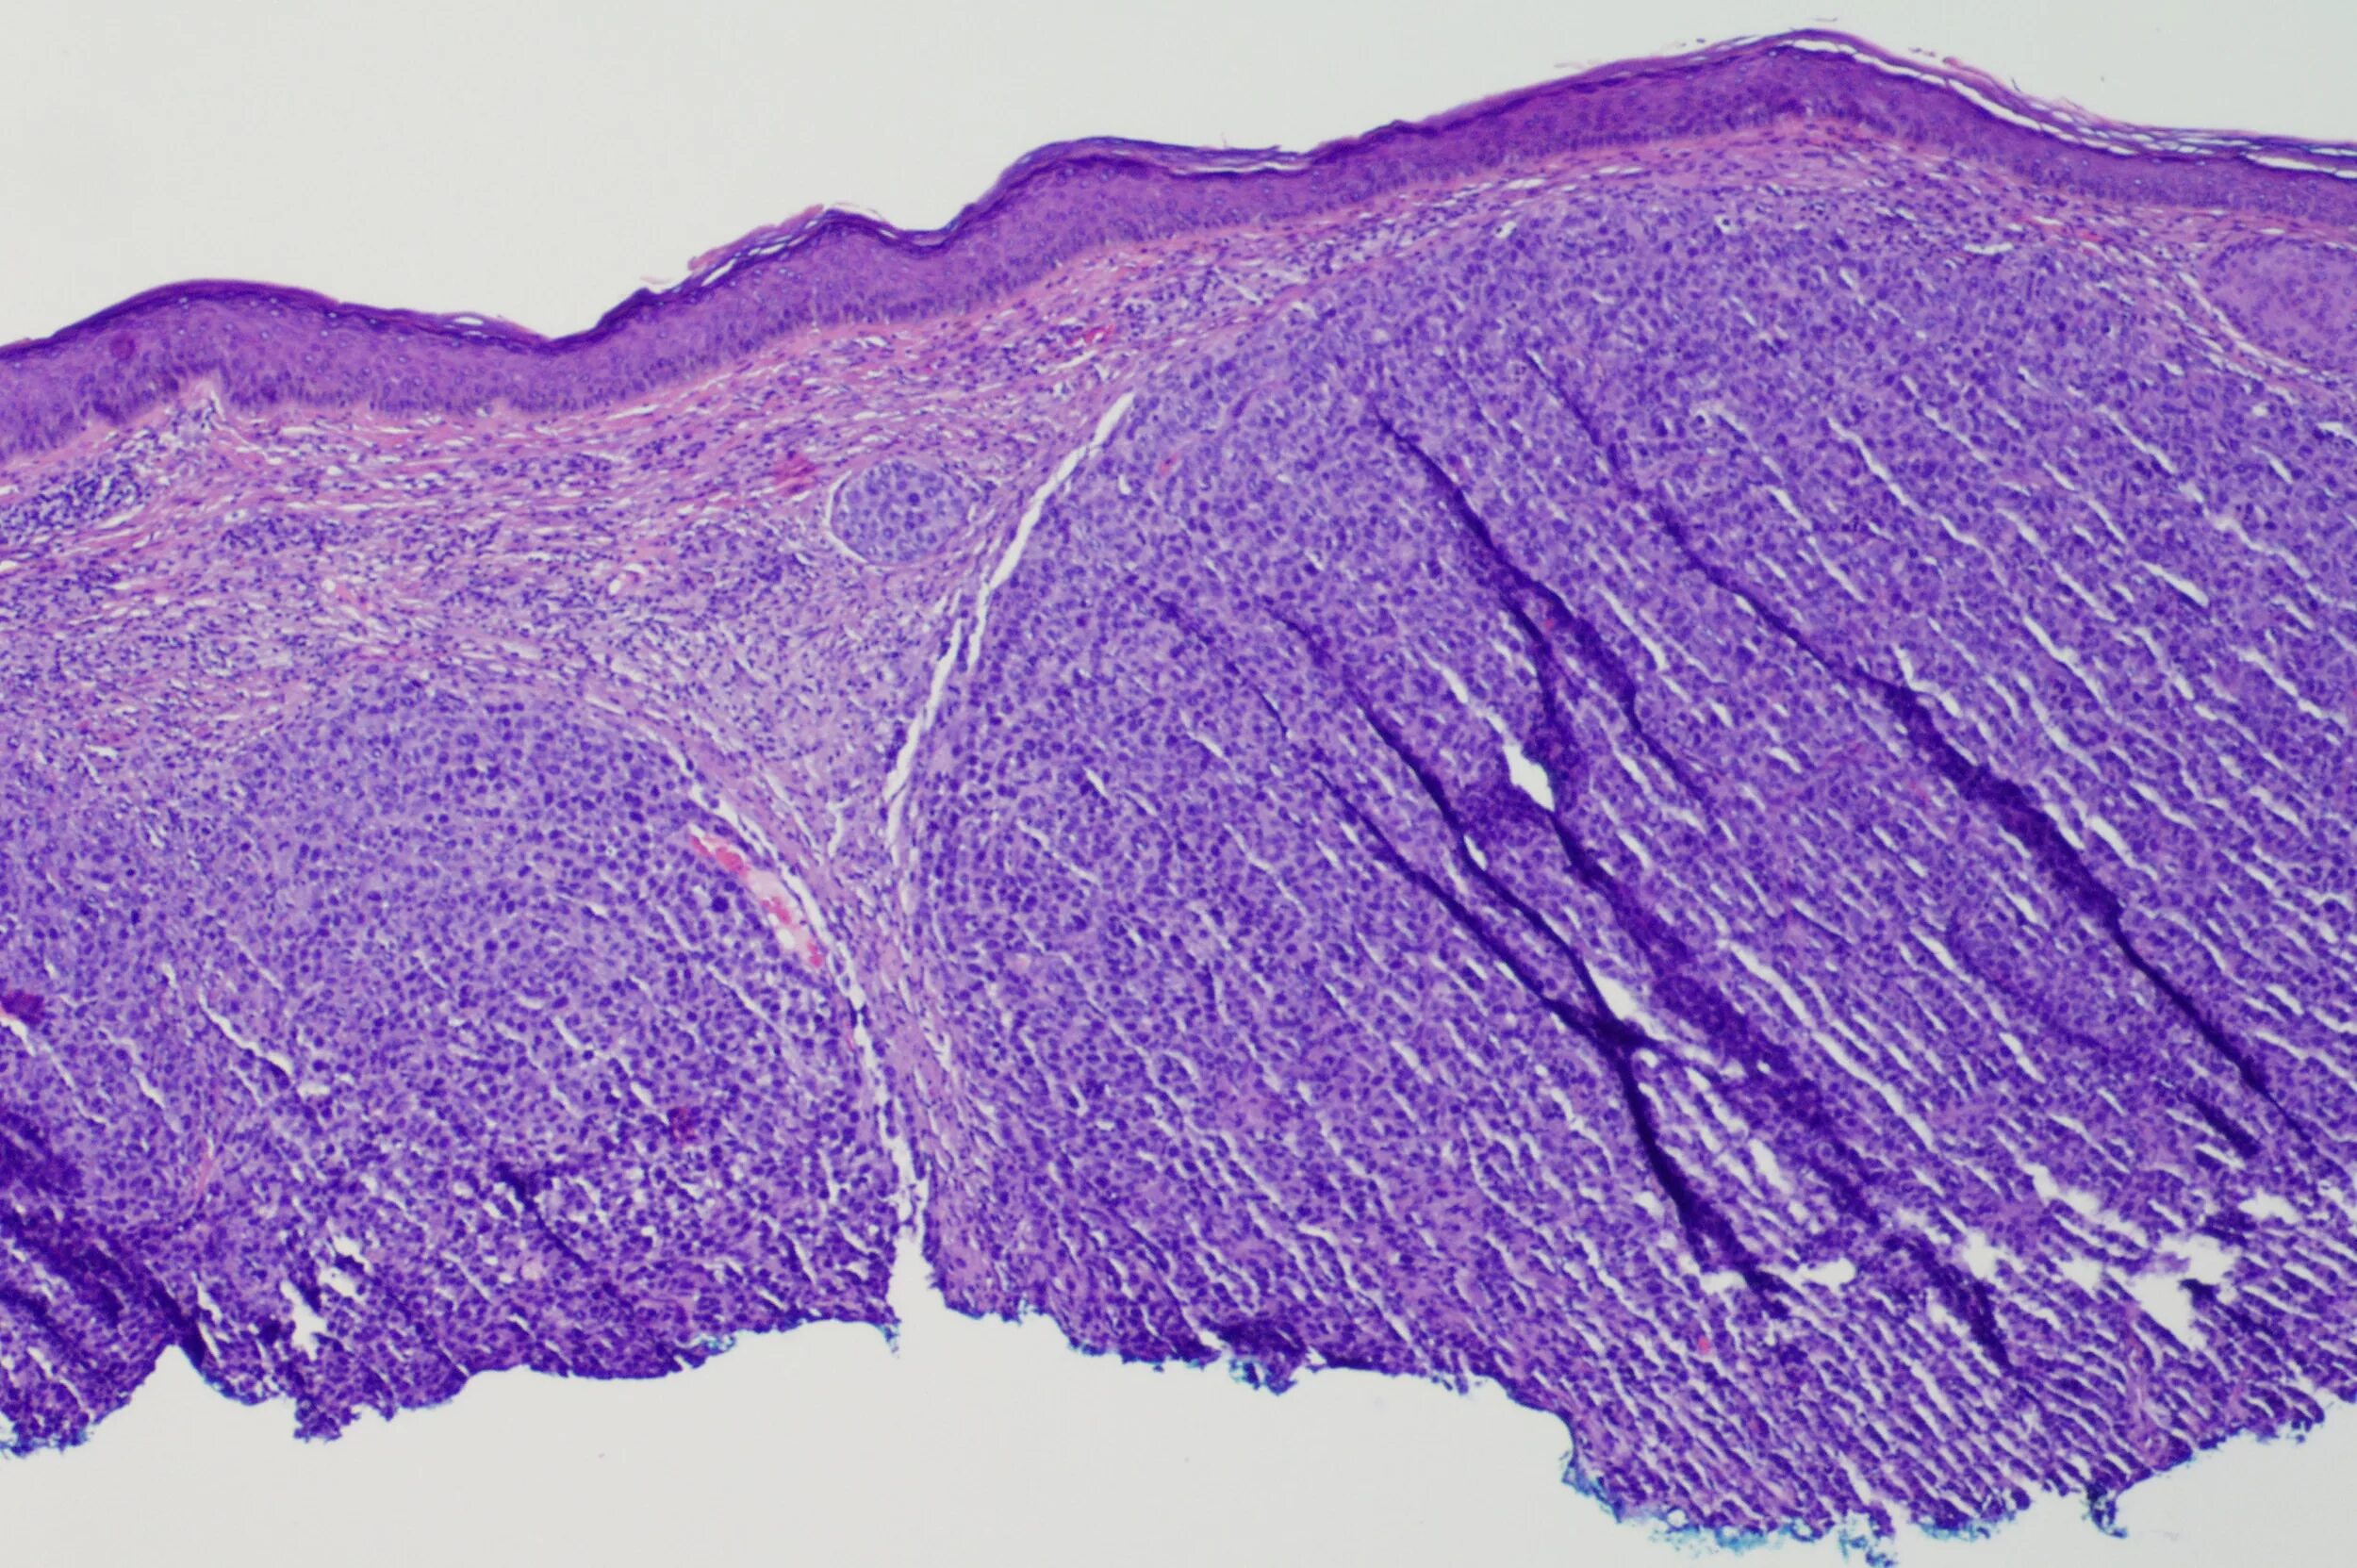

Ошибочная гистология